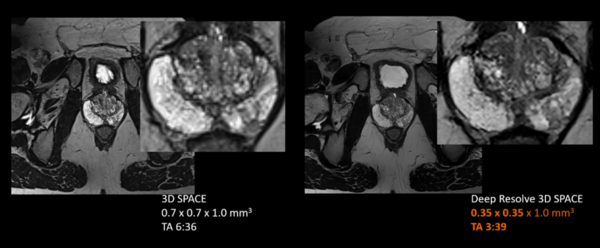

●3D撮像に新たに対応した独自の画像再構成技術Deep Resolveにより,微小病変の描出や腫瘍の境界を明瞭化

Siemens Healthineers独自のAIを活⽤した画像再構成技術Deep Resolveにより,ノイズ低減と空間分解能向上,高速撮像を同時に実現する。最新のソフトウェアでは,この再構成技術を3D撮像に対応させることで,がん診療のための撮像画像にも適⽤を拡大した。これにより,がん診療において求められる微小病変の描出や腫瘍境界の明瞭化を,高速撮像条件下でも安定して提供し,検査時間短縮と高画質化の両立を可能にする。また,3D画像再構成における再構成負荷増加に対応したMaRS(画像再構成 Unit)を搭載することで,画像再構成時間の削減にも取り組む。